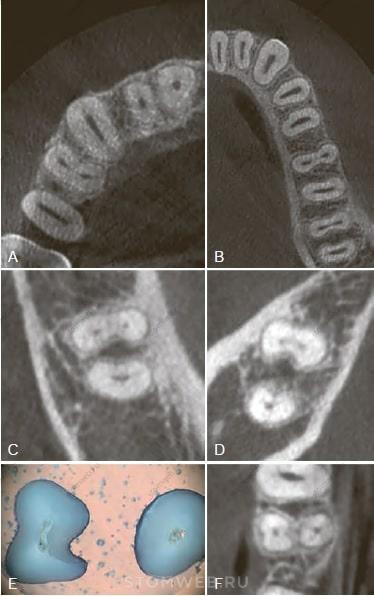

Вертикальные переломы корня часто возникают в зубах с овальным поперечным сечением корня, когда корень шире в язычно-щечном направлении, чем проксимально. Это верхние и нижние премоляры, медиальные корни нижних моляров и нижние резцы (Рис. 21-25, А и В). Такая форма может быть наглядно представлена на поперечных срезах КЛКТ (см. рис. 21-25 А и В). Перелом в этих зубах обычно начинается в щечно-язычной плоскости , а именно, в области наибольшей выпуклости корня (см. рис. 21-25, А и В). Данное заключение на основе изучения большого количества клинических случаев подтверждено также методом анализа конечных элементов. Этот метод четко продемонстрировал концентрирование напряжений на внутренней поверхности дентина в наиболее выступающих частях (то есть со щечной и язычной сторон овального корня) (рис. 21-26).

РИС 21-25 Анатомические предрасполагающие факторы. А) Поперечный срез КЛКТ верхней челюсти, на котором видна овальная форма поперечного сечения каналов клыка и второго премоляра. В) Поперечный срез нижней челюсти, демонстрирующий овальную форму каналов резцов, клыков, премоляров и дистальных корней моляров. Овальное строение в сочетании с эндодонтическим лечением связывают с более высокой вероятностью образования вертикальных переломов корня. С, D) Вогнутость с дистальной стороны медиальных корней нижних моляров также является зоной риска, когда при избыточной инструментальной обработке в сочетании с выпрямлением канала происходит истончение дентинной стенки с концентрацией напряжения в этой области. E, F) Вогнутость небной поверхности щечного корня первого верхнего премоляра (Е - срезы; F - поперечный срез КЛКТ исследования). Такие углубления также могут стать потенциальной зоной риска. Ни одна из вогнутых поверхностей на изображениях С, D, E, F не будет видна на прицельном снимке. Необходимо отметить, что КЛКТ исследование не следует проводить по умолчанию при плановых осмотрах, а только в соответствии с показаниями, обозначенными компетентными органами (Американская Ассоциая Эндодонтистов, Американская академия оральной и Челюстно-лицевой радиологии)

Неравномерная толщина корневого дентина

Механическая обработка каналов часто приводит к неравномерности толщины стенок корней, особенно при выпрямлении искривленных каналов. Неравномерная толщина дентина также образуется при агрессивной механической обработке медиальных корней нижних моляров или первых верхних премоляров, где встречаются проксимальные вогнутости, которые не видны на прицельных рентгенограммах (рис. 21-25, С и D). В таких «зонах риска» увеличение внутреннего напряжения при малой толщине дентина может потенциально привести к перелому. Борозда, которая часто присутствует на небной поверхности щечного корня верхних двухкорневых премоляров, является еще одним примером таких скрытых зон риска (Рис. 21-25, Е и F).